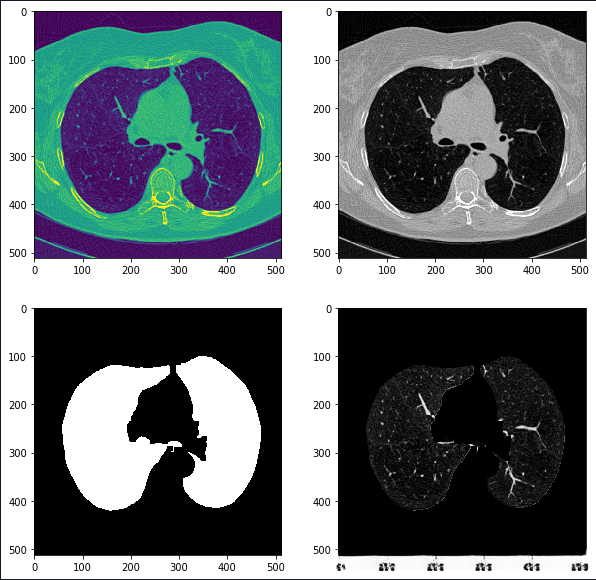

更新:2019.9.14

使用分割后的数据进行训练

经过大约四天的训练后确实比之前有了显著提升

下图左边是预测,右边是根据标注生成的ground truth。